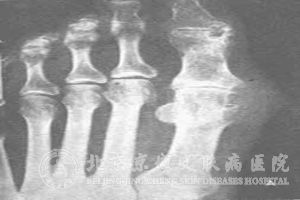

痛风患者需要哪些检查?我们知道痛风患者较常累及的部位是骨关节,根据骨关节的特质,用普通的方法不易察觉。由于痛风给患者的学习、工作与生活都造成了一定程度的影响,所以我们要十分认真的对待痛风,以平和的心态对到,这样会对治疗起到很好的 。那么痛风患者需要哪些检查呢?

北京京城皮肤医院指出:由于骨关节是痛风的常见受累部位。骨骼内有大量钙盐,因而密度较高并与周围软组织形成良好对比。因此,病变的部位要经过X线检查方可显示。普通X线摄片和X线数字摄影简单易行,费用低,可明显的显示四肢骨关节的骨质改变、关节间隙和骨骼性关节面异常及关节肿胀。X线平片常作为了解痛风病人有无骨关节受累的可选影像学检查方法。